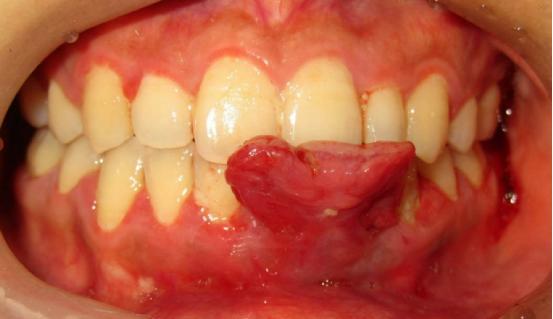

而当小方摘下了口罩,陈莉丽才发现,原来,这位准妈妈的下前牙长了一个核桃般大小的“瘤子”。

“这是妊娠期龈瘤和妊娠期龈炎。”一番检查问询之下,凭着多年的从医经验,陈莉丽很快做出了自己的判断。

又过了2个多月,小方注意到,不仅牙龈出血一直没有好转,连下前牙牙龈也不知道什么时候肿了起来,吃饭时常常会咬到,一碰就出血。小方不敢刷牙,甚至不敢吃东西了,她这才意识到问题的严重性。

陈莉丽在检查中发现,这位准妈妈口腔卫生欠佳,有大量软垢(牙面上黏黏的黄白色脏物)和较多的牙结石,除了下前牙的牙龈瘤以外,其余部位的牙龈也有不同程度的充血红肿。

最终,小方接受了陈医生的治疗方案。经过牙周基础治疗后牙龈瘤体积缩小,陈医生通过牙周手术切除了困扰小方几个月的龈瘤。